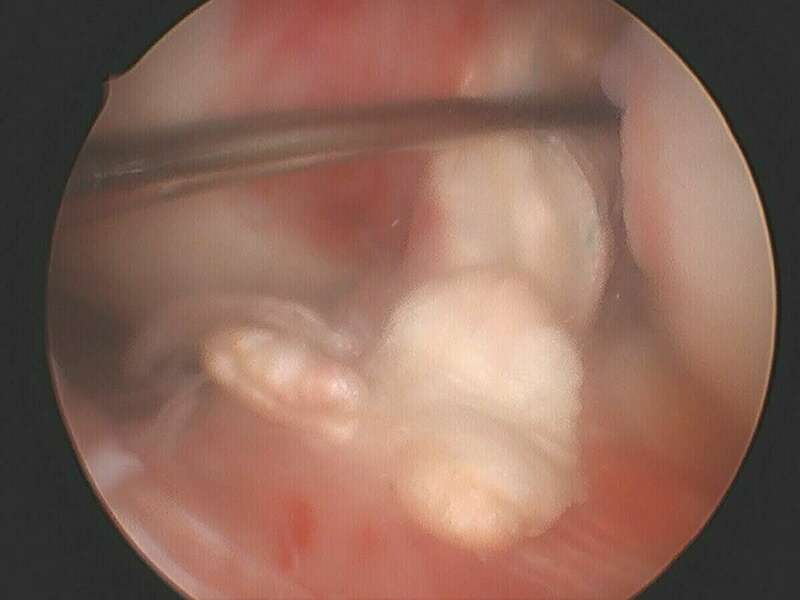

Galerie photo